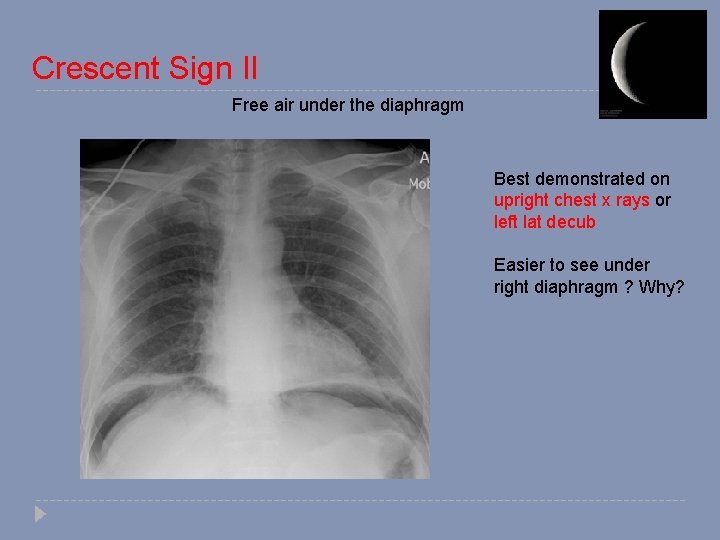

Crescent Sign II Free air under the diaphragm Best demonstrated on upright chest x rays or left lat decub Easier to see under right diaphragm ? Why?